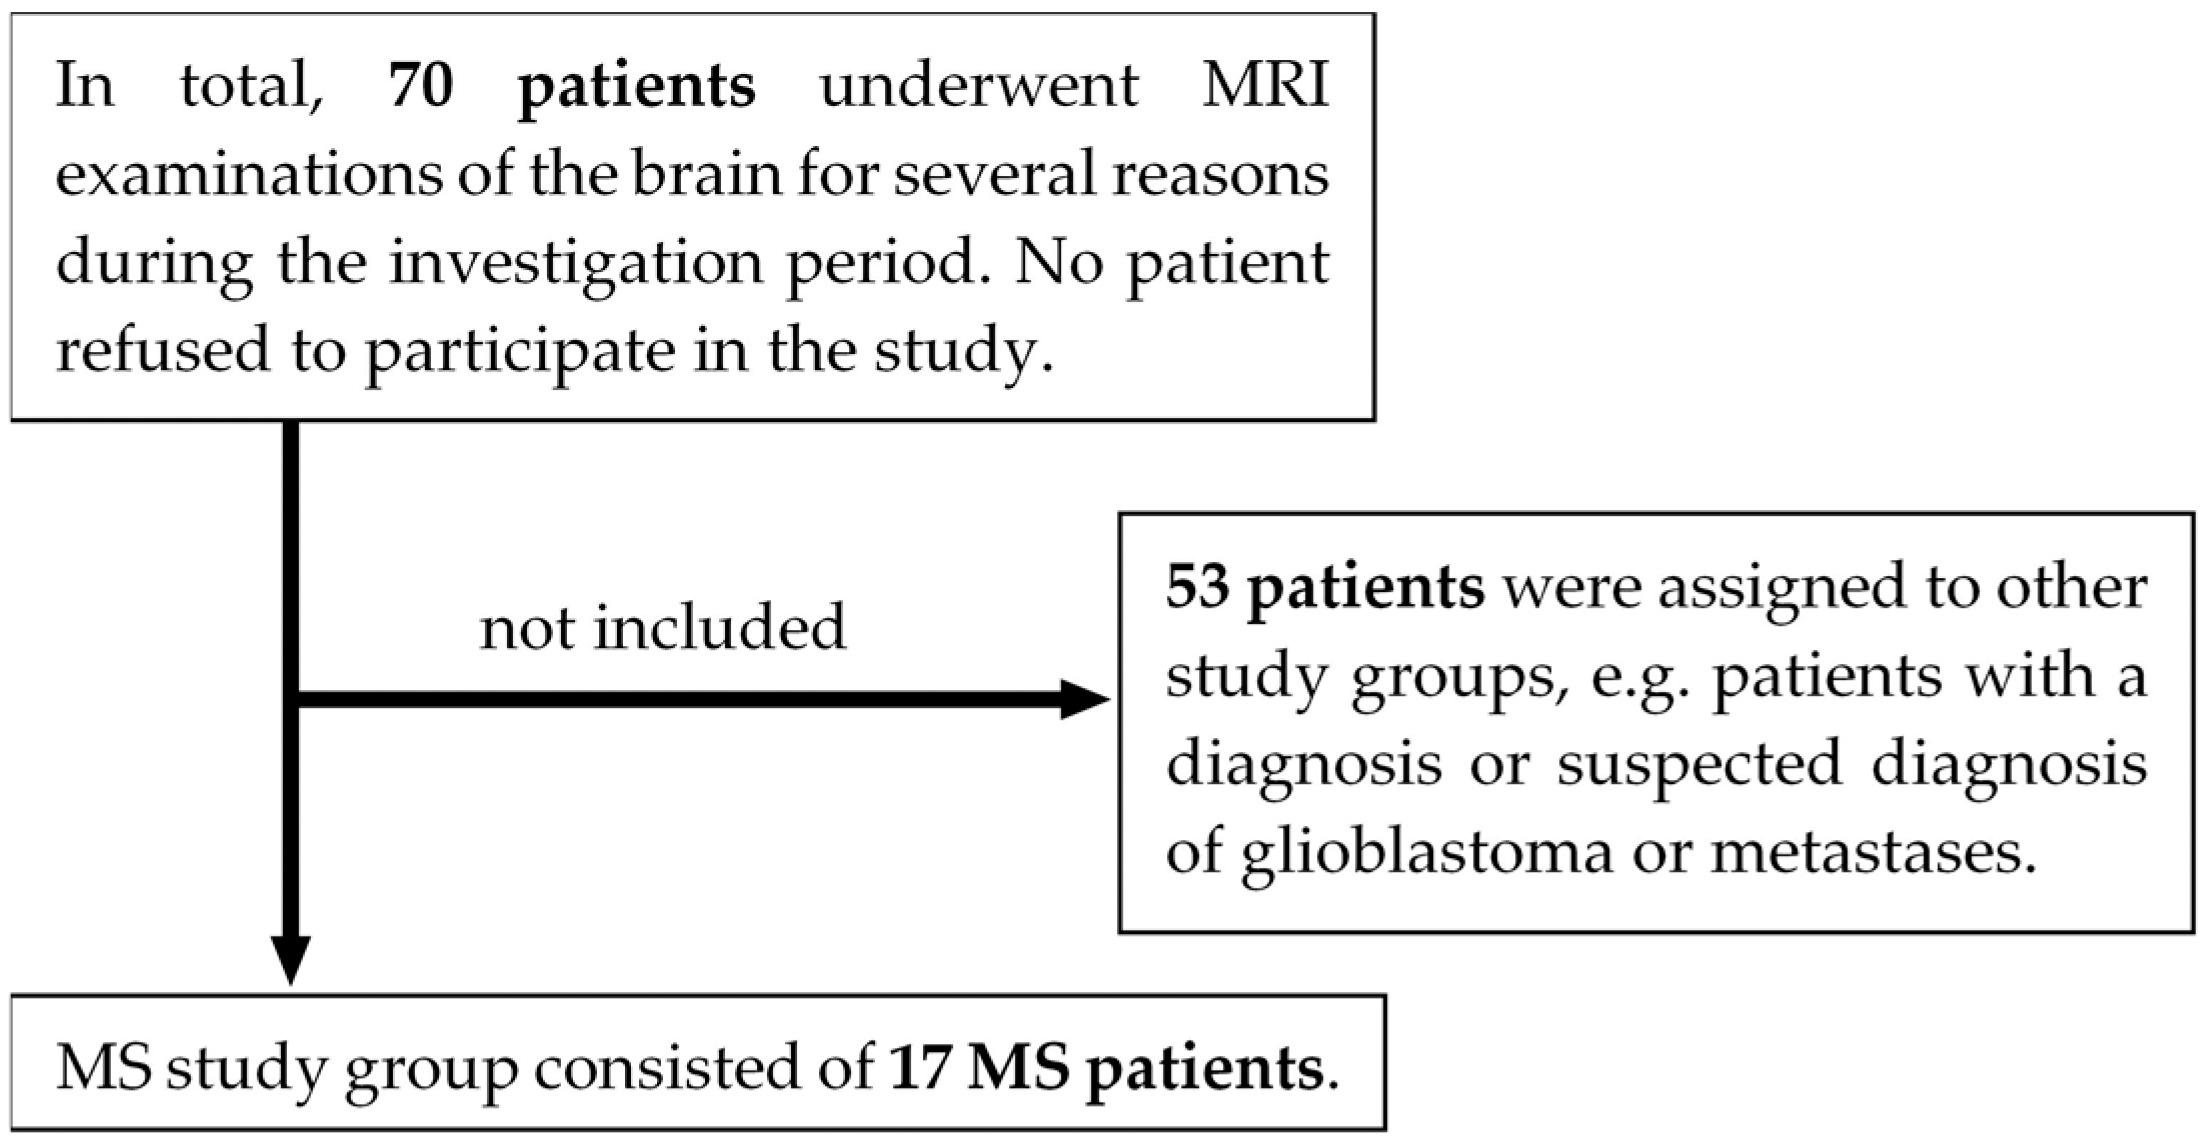

2.1. Study Design